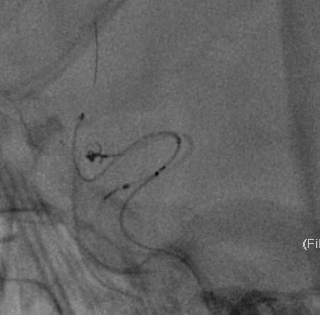

Presgo®微导丝引导支架微导管于基底动脉末端,并预留支架。陆续填塞Jasper®SS弹簧圈4枚,瘤腔填塞致密,撤出支架系统。

术后即刻影像

本病例是基底动脉末端的微小动脉瘤,治疗难度高,适合首选介入栓塞治疗。选择使用加奇Presgo®微导丝、微导管及Jasper®SS弹簧圈,填塞过程顺利,Jasper®SS弹簧圈的柔软性、顺应性表现良好,未见明显踢管现象,电解脱快速顺利。